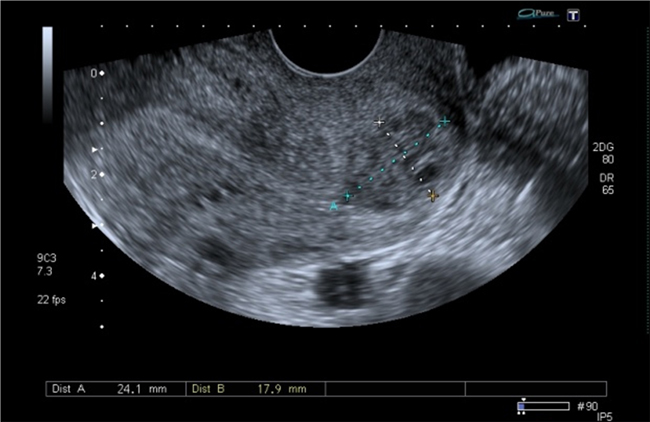

A la paciente se le realizó una prueba en sangre para cuantificar la fracción beta de la gonadotrofina coriónica humana (Abbott Laboratories. Architect.B-hCG Total), que se reportó en 31.819 mUI/ml. También se le tomó una ecografía endovaginal (Toshiba-Xario XG) que mostró la presencia de útero con medidas de 72 × 52 × 54 mm con un cuello de 35 mm con orificio interno cerrado. El endometrio midió 18 mm, sin evidencia de saco gestacional intrauterino y en la región ístmica y cervical, por debajo de las arterias uterinas, se encontró un saco gestacional de 30 mm con presencia de embrión único de 20,6 mm sin presencia de actividad cardiaca fetal (figuras 1 a 4).

A los dos meses asistió a control y se le realizó una ecografía que mostró la presencia de una imagen hipoecoica heterogénea en la zona del istmo de 2 cm de diámetro en el labio anterior, sin presencia de embrión o saco gestacional (figuras 9 y 10).

Figura 9 Presencia de imagen hipoecoica en el labio anterior del cuello uterino que corresponde al tejido cicatricial.